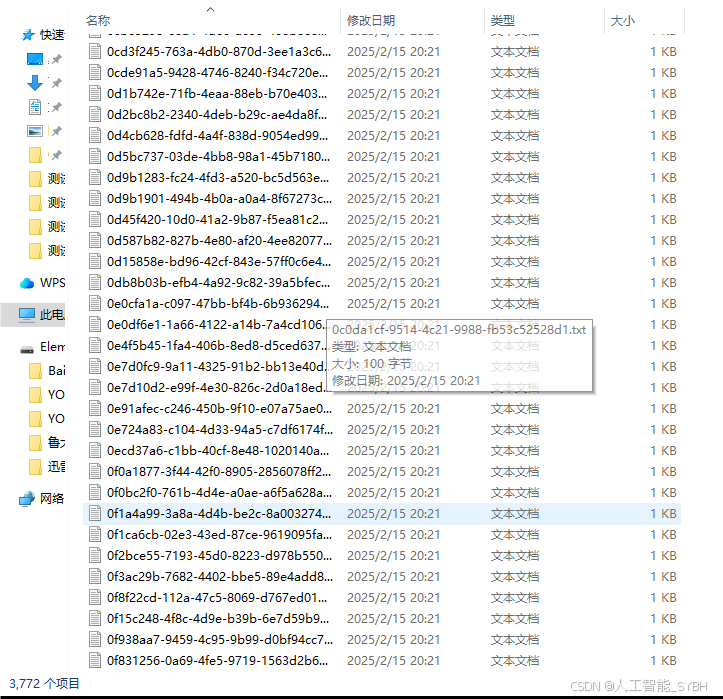

数据标注:

每张图像中的肺炎区域均使用边界框(Bounding Box)标注,并标注对应的类别。

标注格式为YOLO格式(class_id, x_center, y_center, width, height),便于直接用于YOLOv8模型的训练。

names: ['Pneumonia']数据集制作流程

标注数据:使用标注工具(如LabelImg、CVAT等)对图像中的目标进行标注。每个目标需要标出边界框,并且标注类别。

-

转换格式:将标注的数据转换为YOLO格式。YOLO标注格式为每行:

<object-class> <x_center> <y_center> <width> <height>,这些坐标是相对于图像尺寸的比例。 -

准备标签文件:为每张图片生成一个对应的标签文件,确保标签文件与图片的命名一致。